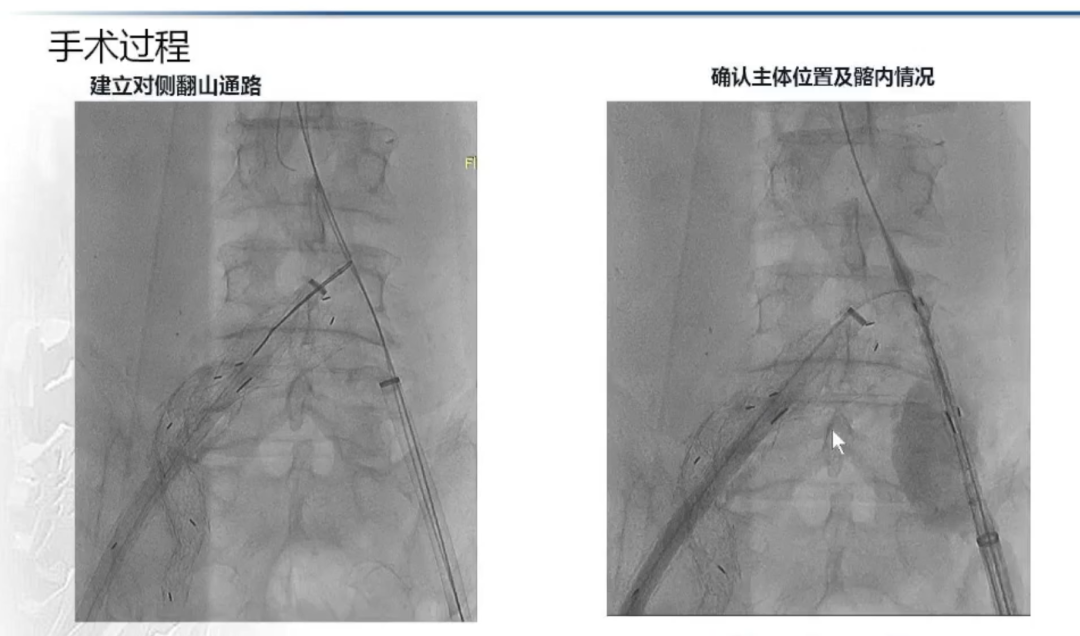

手术过程:根据患者及家属要求保双侧髂内,遂计划双侧髂内重建,右侧优先,左侧髂内情况尝试开通。手术中,先进行造影和翻山建立通路。

翻山建立通路

IBE主体就位与右侧髂内重建

随后IBE主体就位,释放主体并翻山DSF鞘至短腿确认髂内情况,确认髂内健康锚定区情况及长度测量,释放髂内分支。对髂内支架狭窄处扩张,输送和释放第二枚髂内分支并手推造影确认通畅,IBE主体及各连接处后扩。

左侧髂内动脉超选与重建

右侧髂内动脉重建完成后,建立对侧翻山通路,再次确认主体位置及左侧髂内动脉情况。左侧髂内超选困难,经反复确认导丝配合导管超选真腔,手推造影确认髂内情况后释放远端VB,释放左侧髂内分支HGB并确认通畅情况。最后按常规EVAR置入腹主动脉支架主体,超选入主体短腿内对接IBE主体释放桥接喇叭腿。